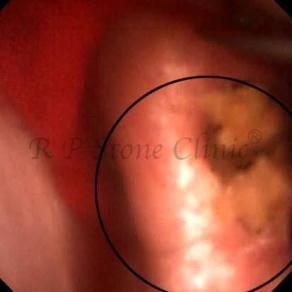

The Below Images Show Small Stones attached to the Renal Papillae.